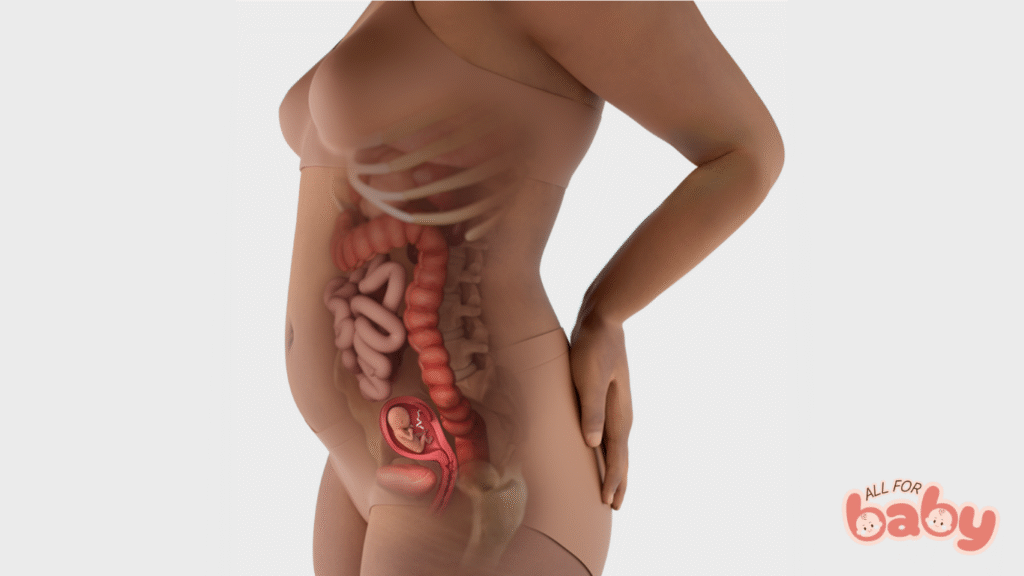

Ở tuần thai thứ 10, bé có chiều dài khoảng 3–4 cm (kích thước bằng một quả dâu tây nhỏ) và nặng khoảng 4–5 gam. Đây là cột mốc đáng nhớ vì:

Bé đã hoàn tất phần lớn những bước phát triển quan trọng của giai đoạn phôi thai, và chính thức được gọi là thai nhi.

Tay, chân, ngón tay và ngón chân đã rõ rệt hơn.

Xương và sụn bắt đầu hình thành, răng sữa cũng đang phát triển bên dưới nướu.

Các cơ quan nội tạng chính như gan, thận, ruột, dạ dày đã bước vào giai đoạn hoạt động.

Bé có thể cử động nhẹ, co duỗi tay chân, dù mẹ chưa cảm nhận được.